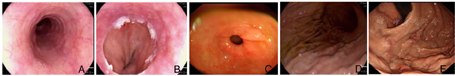

胃底粘液湖清亮,可见多发迂曲曲张静脉,最大直径0.6 cm,红色征阳性,未见活动性出血及血栓头。内镜下诊断(图1):胃底静脉曲张(LgfD1.0Rf1);慢性萎缩性胃炎(C1)。

注:A:食管;B:贲门;C:胃窦;D:胃体;E:胃底